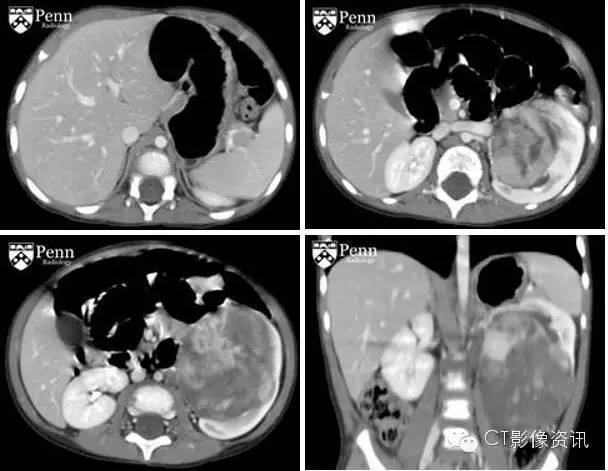

28个月大的男孩伴有腹部肿块

病史 男,28个月,一周前发现左腹部可触及明显肿块。

增强CT图像如下

CT显示在L1椎体破坏性病变(在先前的图像并未显出)